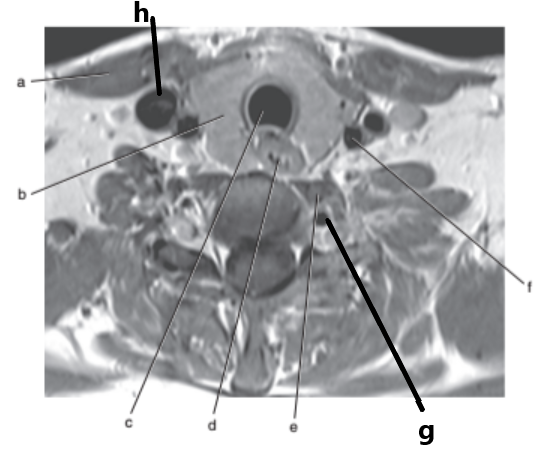

What imaging plane is this ?

transverse

What is letter f ?

Spinal cord

What is letter h ?

Internal jugular vein

Vocal cords